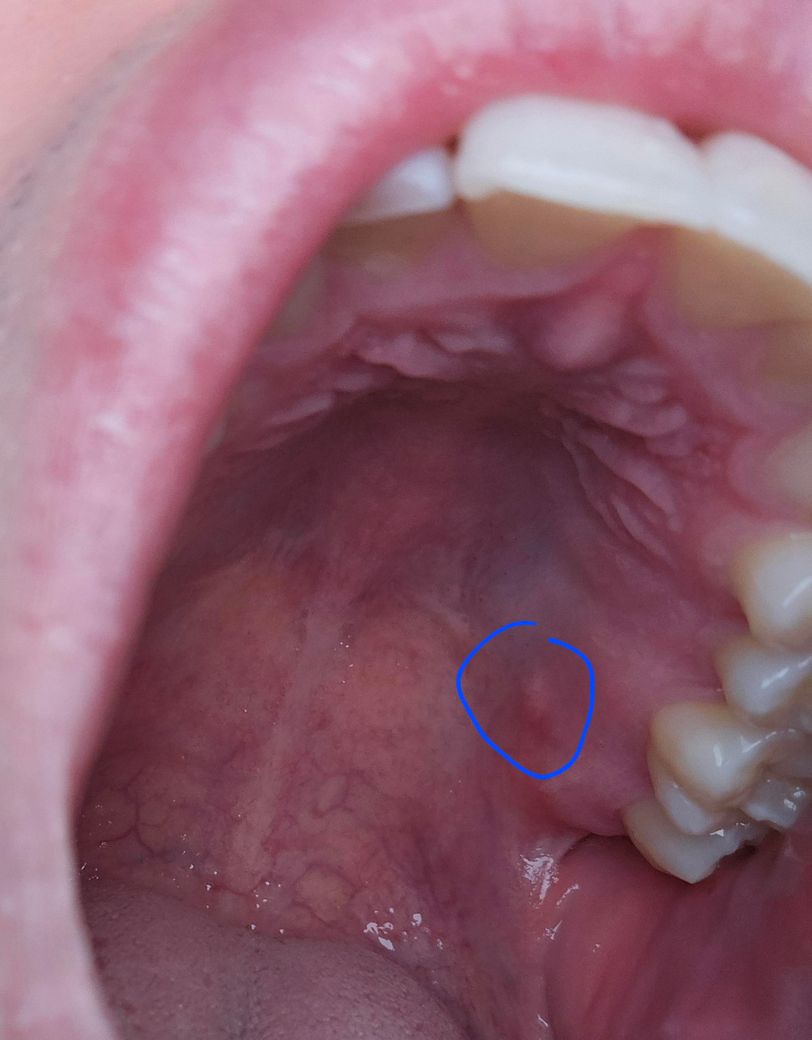

입천장에 이빨이 만져져요 괜찮은건가요?

입천장쪽 한쪽에만 살짝 나와있는 이빨이 만져집니다. 치료해야하는지 그냥 놔둬도 상관이 없는건지 궁금합니다. 어떻게 하는게 좋을까요??

• 1번 째 사진

사진으로는 치아의 유무를 정확하게 확인하기 어려워 보입니다. 내부에 매복되어 있는 사람이라면 굳이 발치를 하지 않아도 될 수 있습니다. 하지만 해당 부위가 불편하거나 지속적으로 문제가 생긴다면 사랑니를 발치해 주는 것이 좋을 수도 있습니다.

입천잔 부위에 과잉치가 있을 수도 있고 이런 경우 엑스레이를 찍어봐야 알 수 있습니다. 단순 골 융기일 수도 있습니다. 사진상으론 알 수 있는게 많지 않고 일단 치과를 가보시는 것을 추천드립니다.

치아가 맞는 지 부터 확인을 해보시는 것이 좋겠습니다. 일반적으로 치아가 있을 곳은 아닙니다.

입천장쪽 한쪽에만 살짝 나와있는 이빨이 만져지는 경우에는 입천장 쪽에 매복된 치아가 표면 가까이에 위치해 만져질 수 있습니다. 우선은 정확한 상태 확인을 위해 엑스레이 촬영이 필요로 되기에 치과진료를 받길 권합니다.

만족스러운 답변되셨으면 합니다.